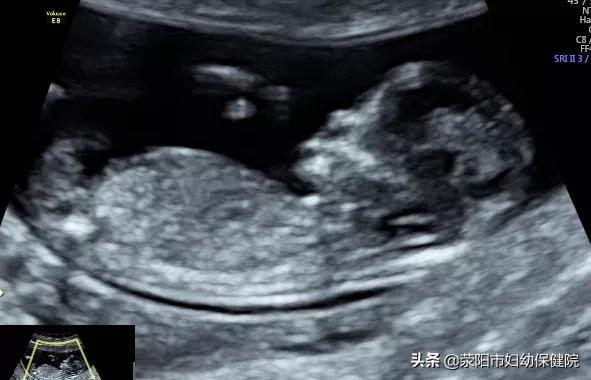

2.孕18周左右系统筛查:

比NT时候的胎儿发育会更大一些,更加利于观察,尽早的发现胎儿解剖结构中较大的畸形。